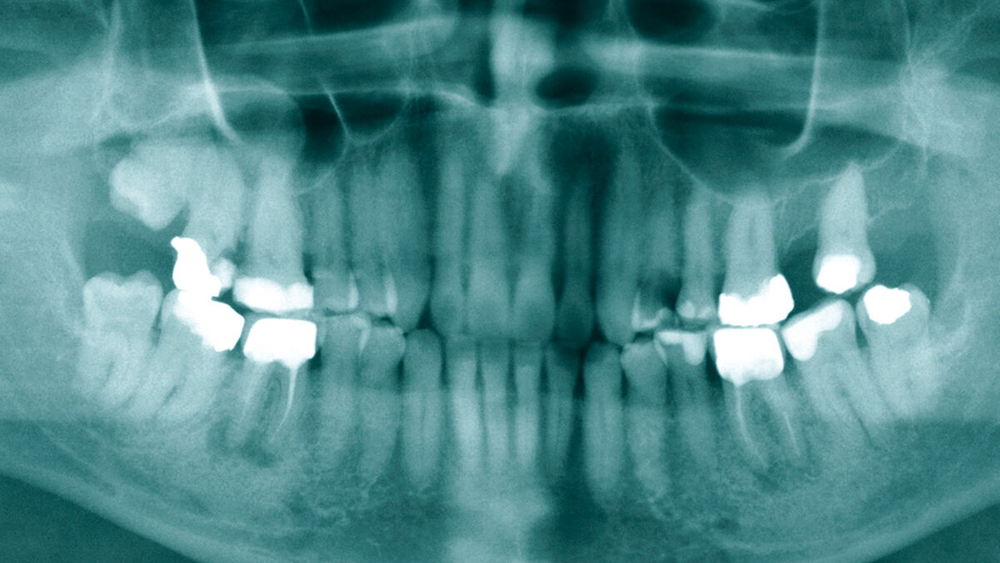

Eine angefertigte Panoramaschichtaufnahme zeigte ein konservierend und prothetisch unvollständig versorgtes Gebiss mit einem wurzelkanalbehandelten Zahn 36 und einer apikalen Osteolyse (Abbildung 1). Angesichts des ausgedehnten Abszessgeschehens wurde eine notfallmäßige Computertomografie zur erweiterten Diagnostik durchgeführt. Hier zeigte sich ein großflächiger Abszess des linken Unterkiefers mit einer Ausbreitung in die Tonsillenregion sowie in die Halslogen mit begleitenden einschmelzenden Prozessen (Abbildung 2). Zusätzlich zeigten sich im initial angefertigten Blutbild des Patienten ein Procalcitonin von 10 ng/ml, eine Blutglukose von 1.034 mg/dl sowie ein HBA1c-Wert von 13 Prozent. In der Zusammenschau der Befunde konnte somit von einem beginnenden septischen Krankheitsbild ausgegangen werden.